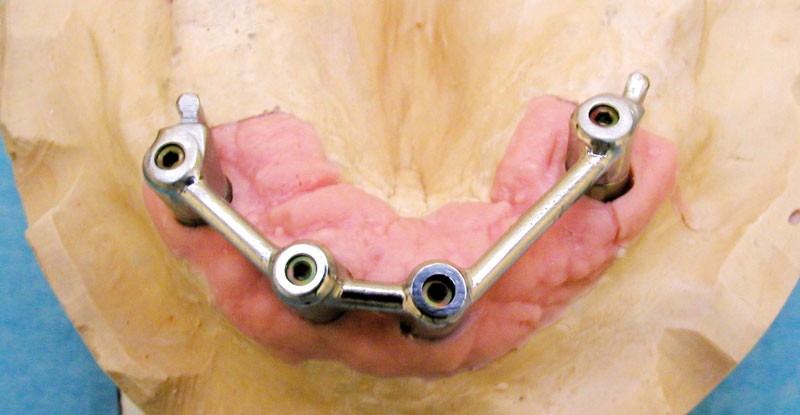

Le choix d’une prothèse amovible complète supra implantaire (PACSI), par opposition à une prothèse fixe implanto-portée, est guidé par différents facteurs. Nous retrouvons en premier lieu le degré de résorption osseuse, le niveau de décalage des bases osseuses, l’espace inter- arcades, la qualité osseuse, le volume osseux disponible, les moyens financiers du patient, et le refus de techniques de chirurgie lourde pour les personnes âgées (fig. 1 et 2).